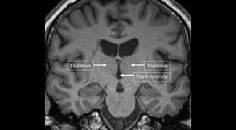

MS Minute: Cognitive Dysfunction in People Living with Multiple Sclerosis

Sophia Marchetti, BASc; Anthony Feinstein, MDSophia Marchetti, BASc; Anthony Feinstein, MD - MS & Immune Disorders